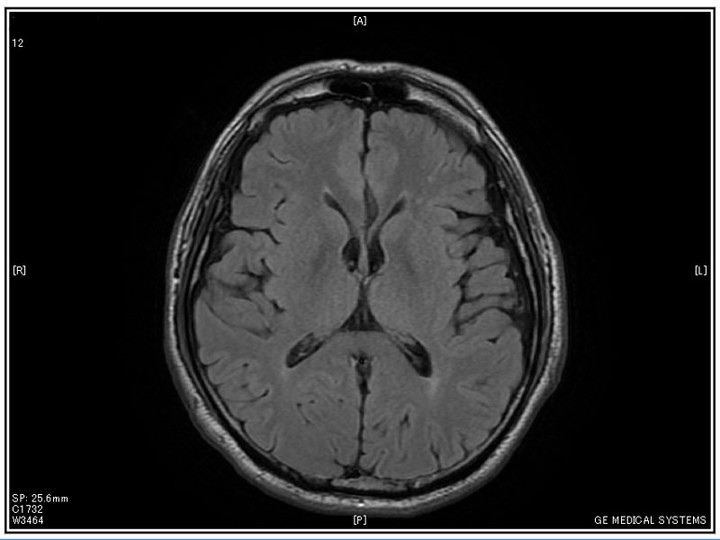

脳ドック

脳ドックを受けた。

結果を「CD-ROM」でもらった…